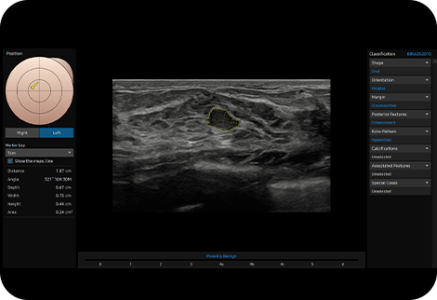

The feature, which analyzes selected lesions in the breast ultrasound study and shows the analysis data, applies BI-RADS ATLAS* (Breast Imaging-Reporting and Data System, Atlas) to provide standardized reporting; and helps diagnosis with the streamlined workflow.